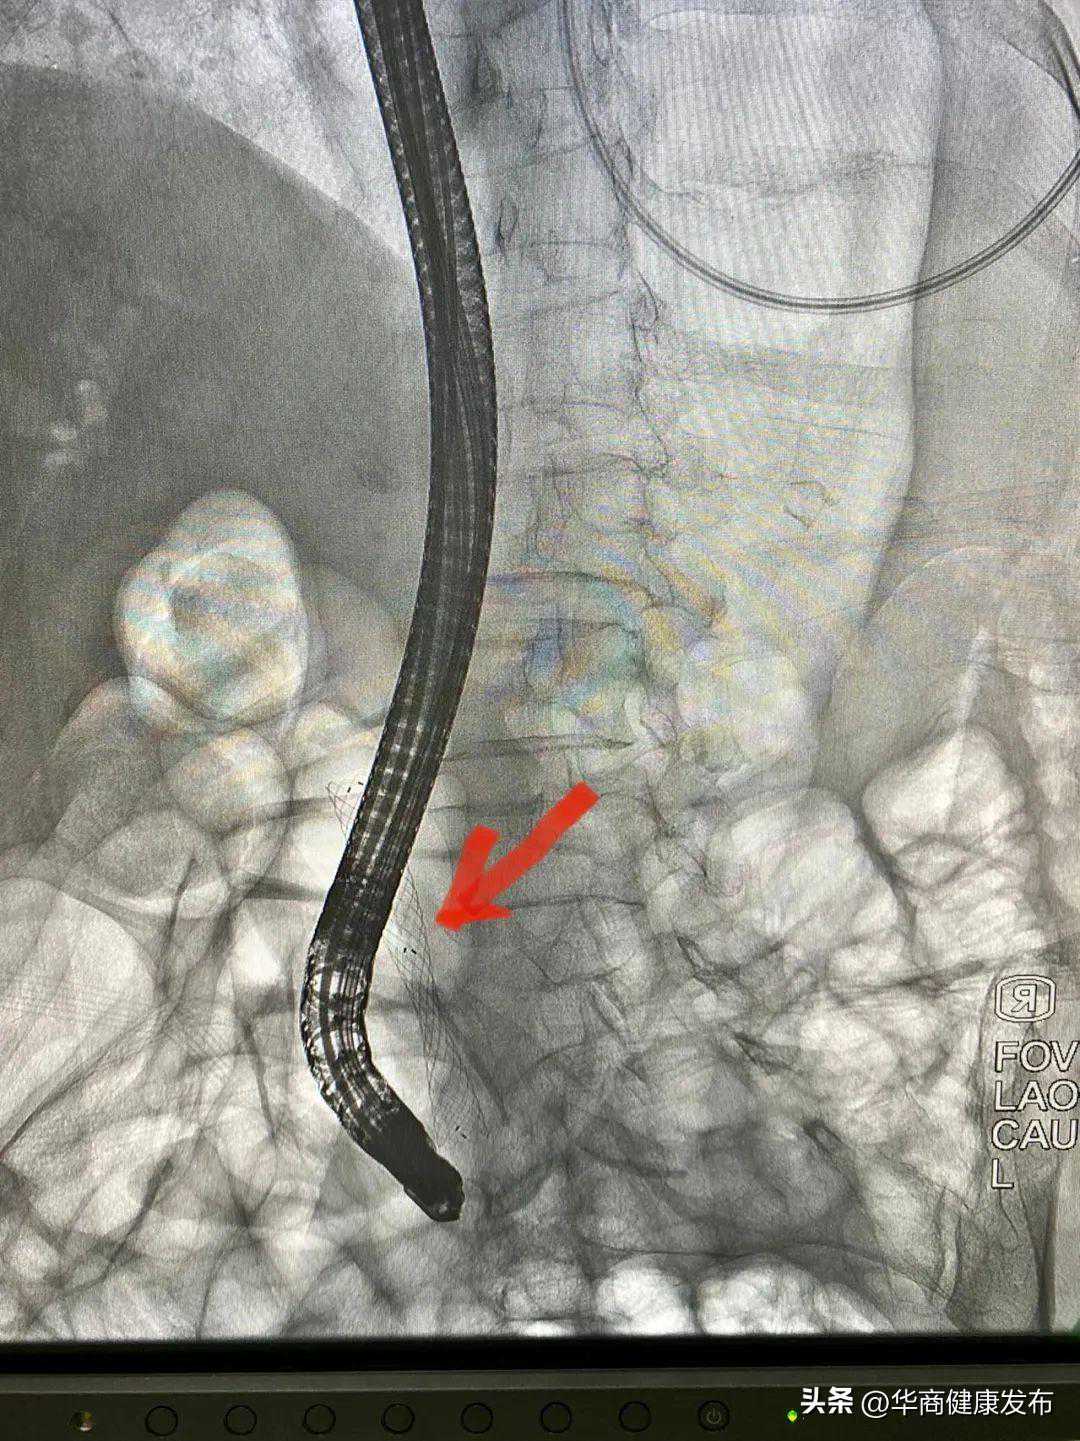

术中,卢王主任使用十二指肠镜顺利插入十二指肠乳头,造影显示胆总管近十二指肠入口处狭窄,为进一步明确狭窄性质,进行了一次性使用电子胰胆管内窥镜直视下的胆道探查。在一次性胆道镜直视下可见胆总管下段新生物形成,表面凹凸不平,充血粗糙,局部狭窄形成,直视下精准活检成功明确诊断,并放置了胆道金属支架。整台手术仅耗时约30分钟,顺利完成。术后王奶奶黄疸逐渐减轻,食欲增加,恢复正常生活。

直视下精准活检